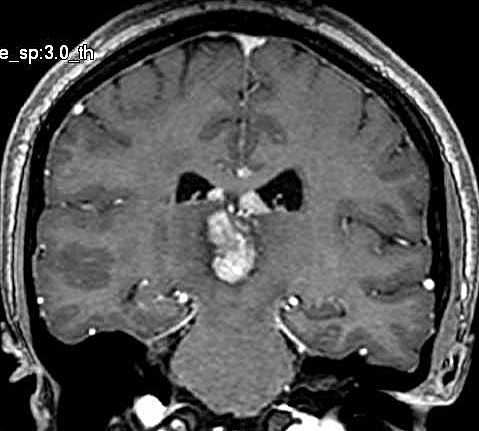

| Fem. 17a. |

| Nódulo sólido homogêneo preenchendo o III ventrículo, com limites precisos, com hipossinal em T1 e hipersinal em T2 e FLAIR, que se impregna por contraste paramagnético. Lesão menor implantada no assoalho do IV ventrículo provavelmente representa disseminação por via liquórica. |

| F. 17a. Tumor teratóide rabdóide atípico de III ventrículo. RM | HE | VIM, GFAP | HHF35, desmina, 1A4 | AE1AE3, EMA |